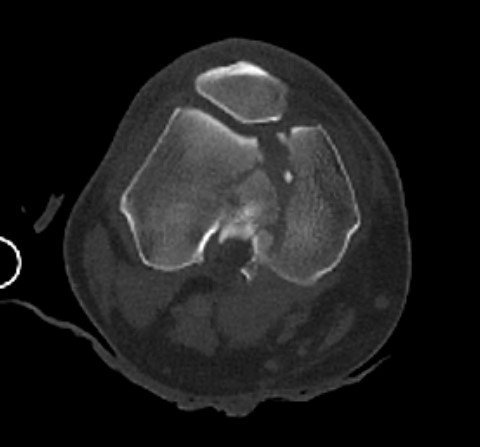

Type C: Complete articular

Xray / CT

Dual plate

Indications

Significant comminution

Loss of medial cortical buttress